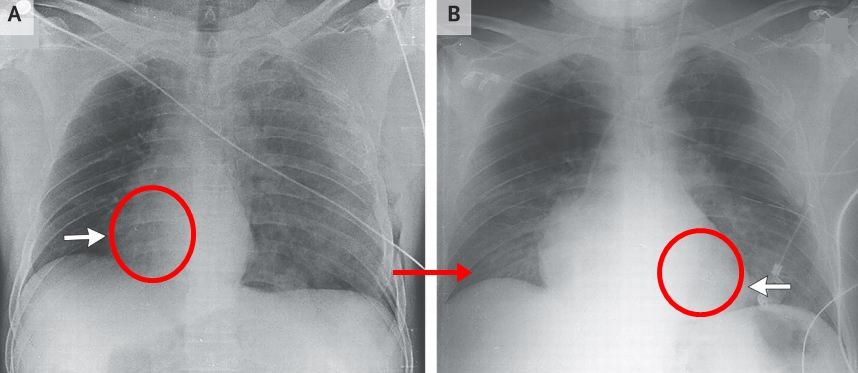

심장은 인간의 몸에서 특정한 위치에 자리잡고 있으며, 그 구조와 기능에 따라 여러 중요한 역할을 수행합니다. 심장은 흉강 중앙에 위치해 있으며, 두 개의 폐 사이에 자리잡고 있는 '가슴뼈'(sternum)와 가까운 위치에 있습니다. 즉, 심장은 왼쪽으로 살짝 치우친 형태로, 아래쪽은 횡격막(diaphragm)이라는 근육에 의해 지지받고 있습니다. 이러한 구조는 심장이 외부 압력으로부터 보호받을 수 있도록 도와줍니다.